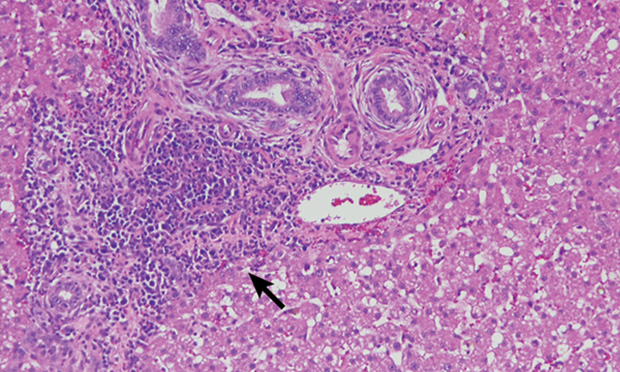

Triaditis Veterinary Clinics Small Animal Practice

Liver And Gall Bladder Disease In Your Cat Cholangiohepatitis Triaditis Ron Hines Vetspace 2nd Chance The Animal Health Website

Triaditis Syndrome